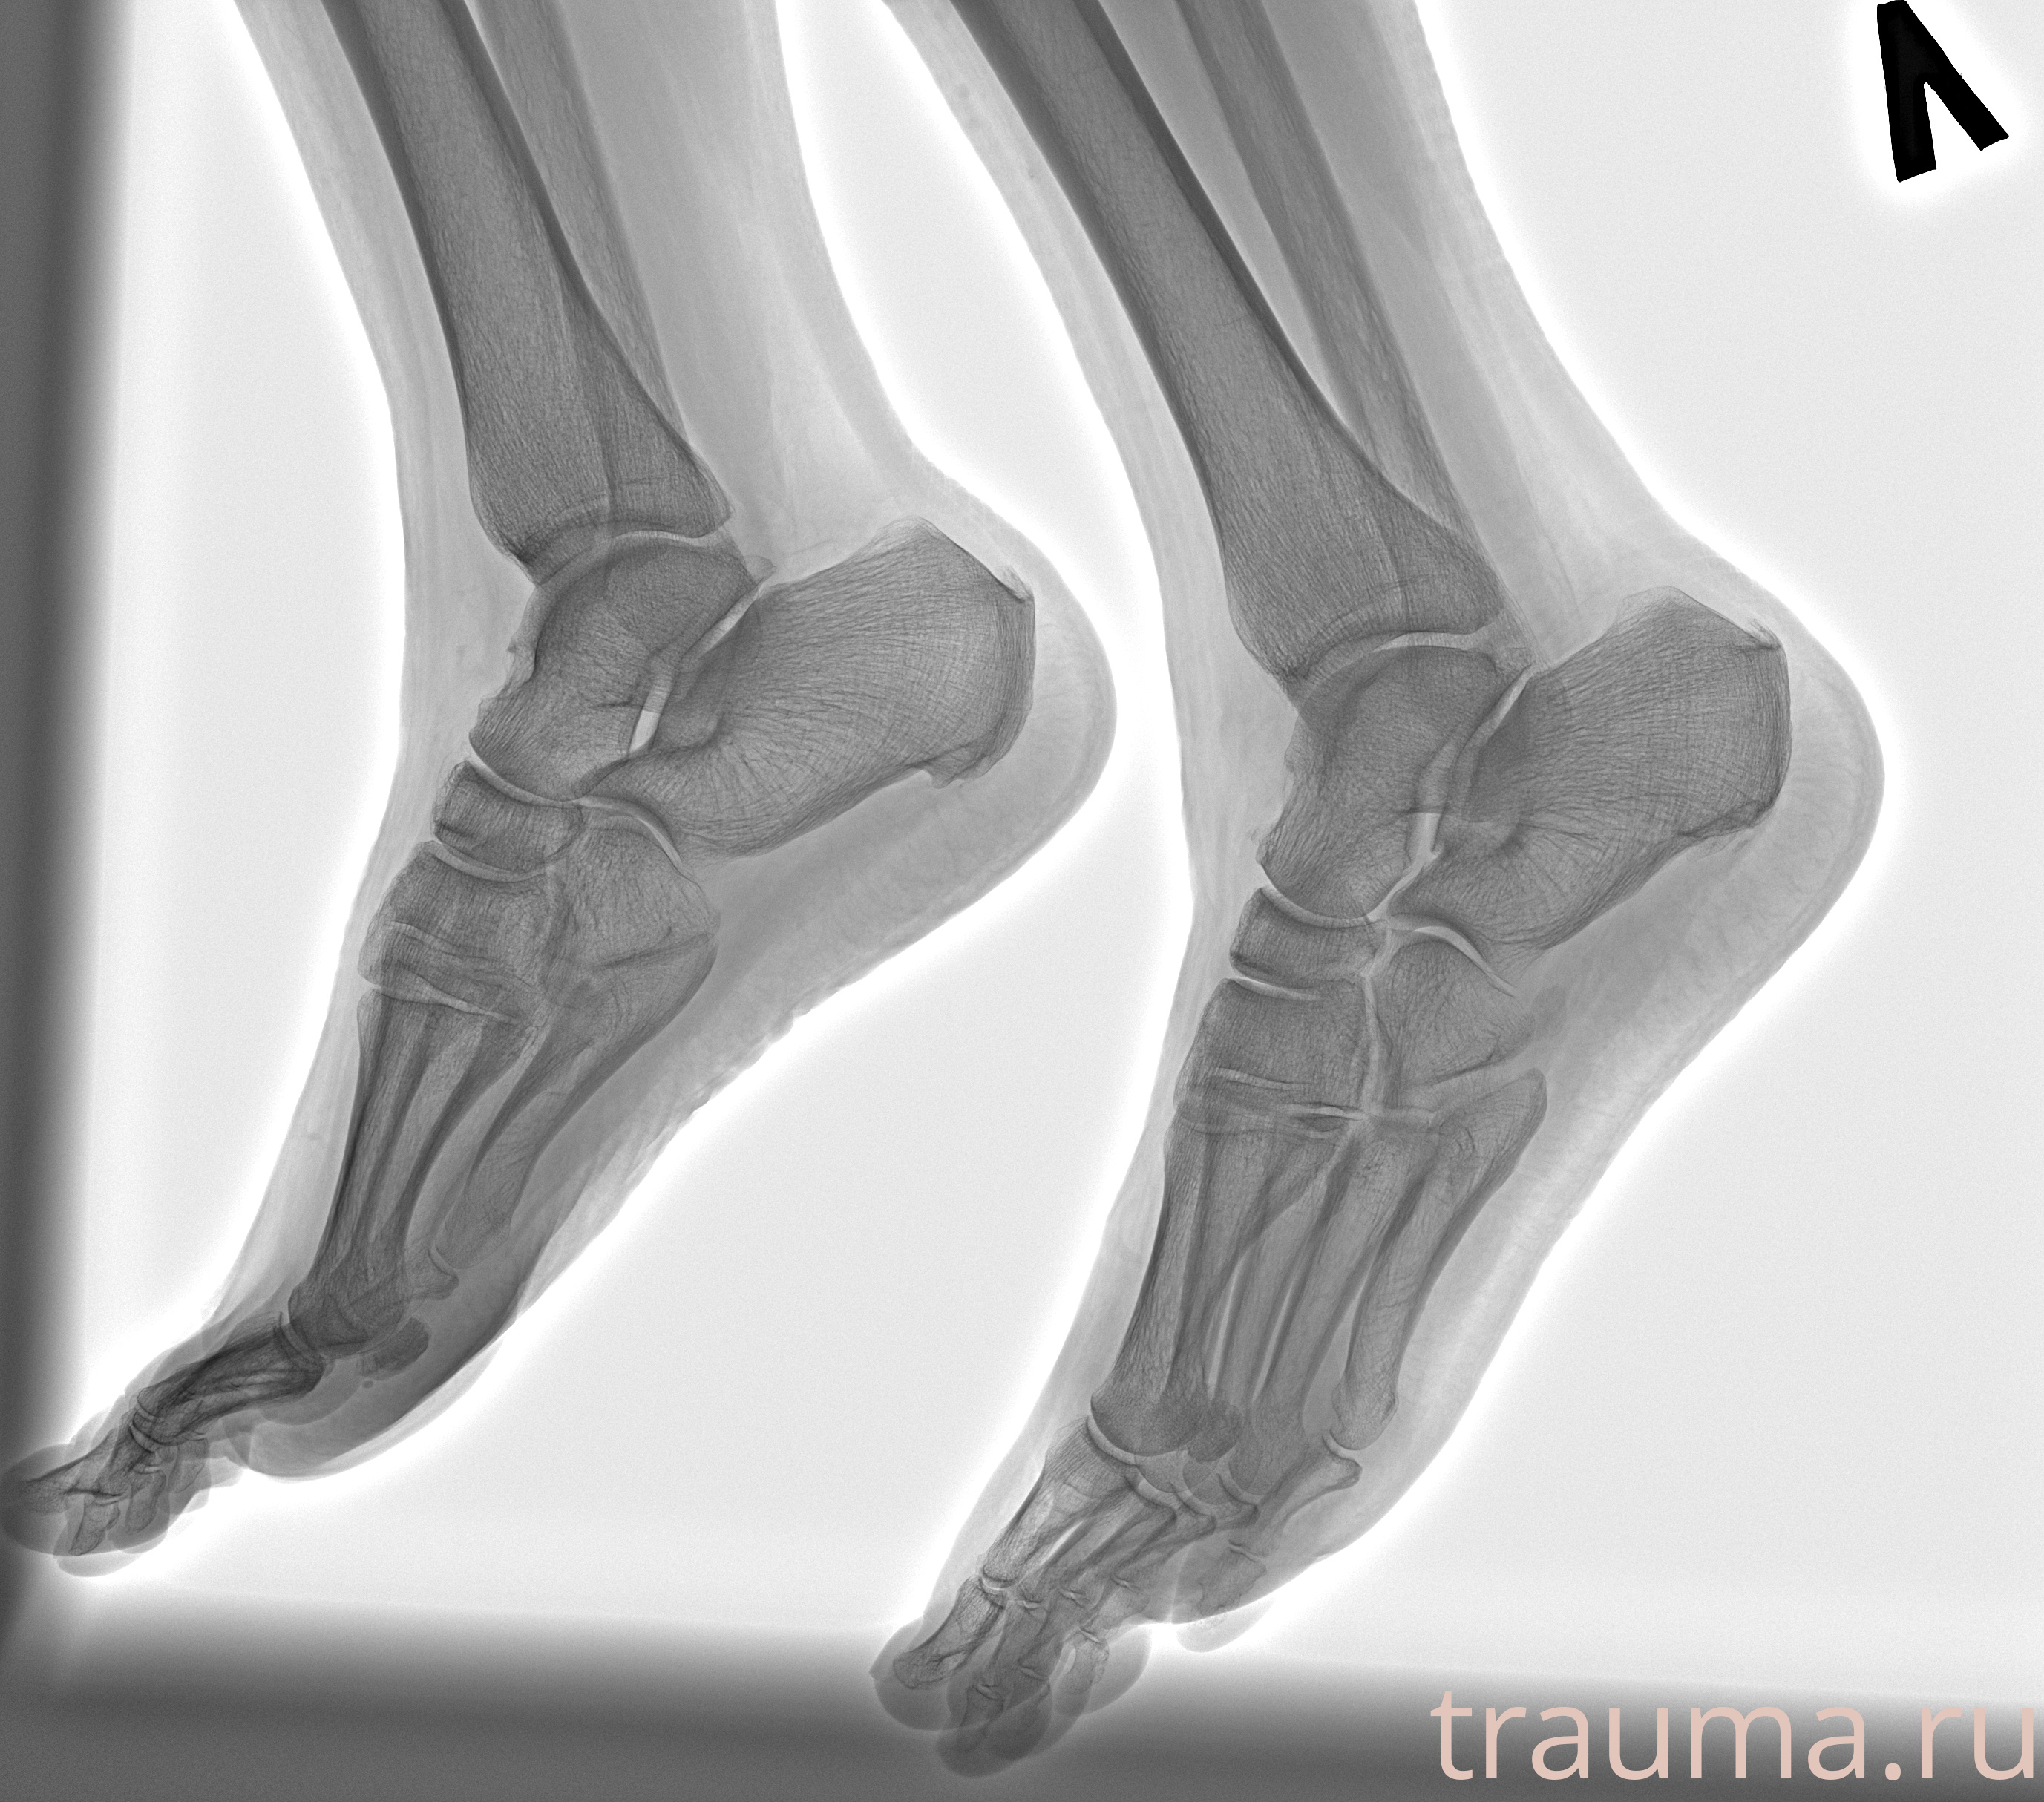

Рентгенограммы

Рентген на дому: по вашему адресу приезжает врач-рентгенолог, травматолог-ортопед с мобильным рентгеновским аппаратом, проводит диагностику травмы или заболевания, делает необходимые рентгенограммы, дает рекомендации по дальнейшему лечению. Получить качественные снимки в домашних условиях возможно благодаря уникальной методике, разработанной МосРентген Центром для института  Склифосовского